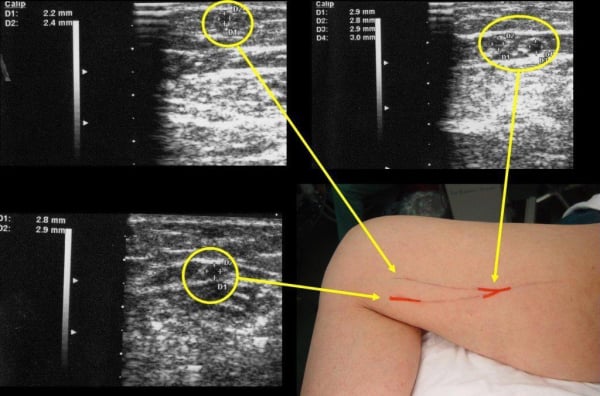

Ένα σύγχρονο και τεχνολογικό ιατρείο αγγειοχειρουργού θα ενσωματίζει πολλές σύγχρονες τεχνολογίες και πρακτικές προκειμένου να παρέχει υψηλής ποιότητας φροντίδα για προβλήματα που σχετίζονται με τον αγγειακό σύστημα. Ορισμένα χαρακτηριστικά που μπορεί να έχει ένα τέτοιο ιατρείο περιλαμβάνουν: